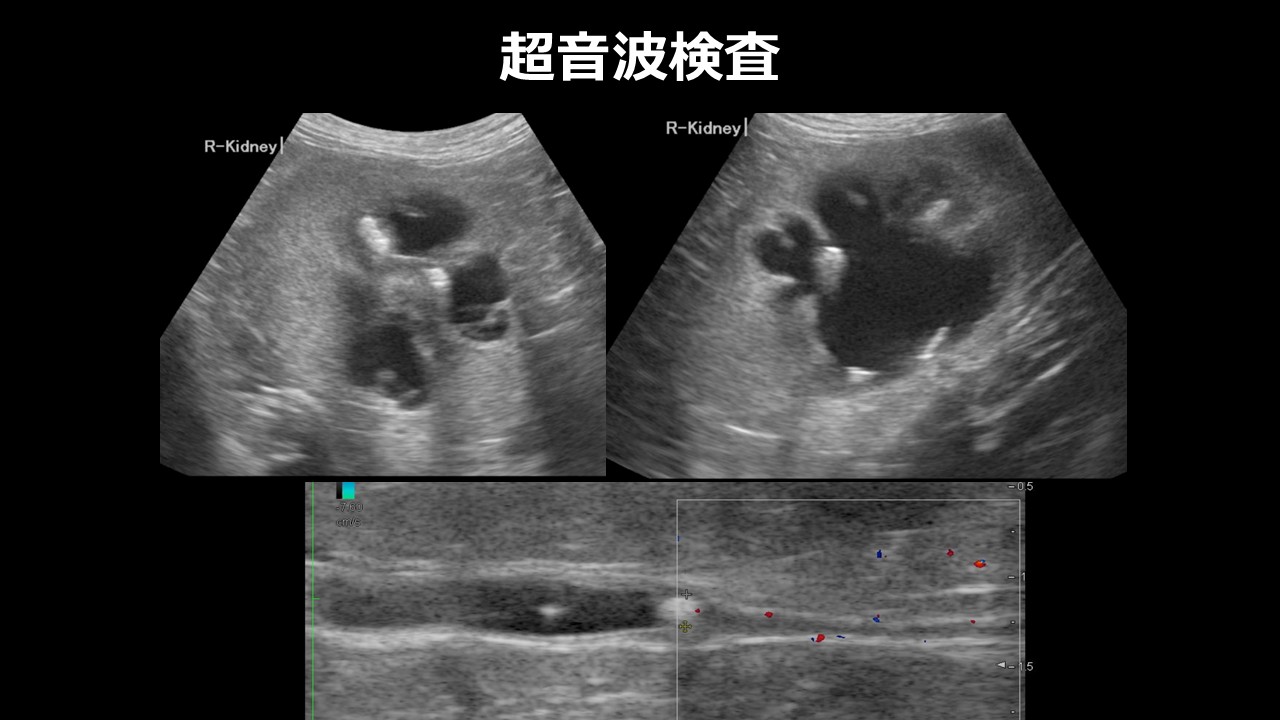

・超音波検査(エコー):

尿管や腎臓内の尿の流れ、水腎症の有無を確認できます。

⇨腎盂の拡張を認める場合は、尿管閉塞を強く疑う所見となります。